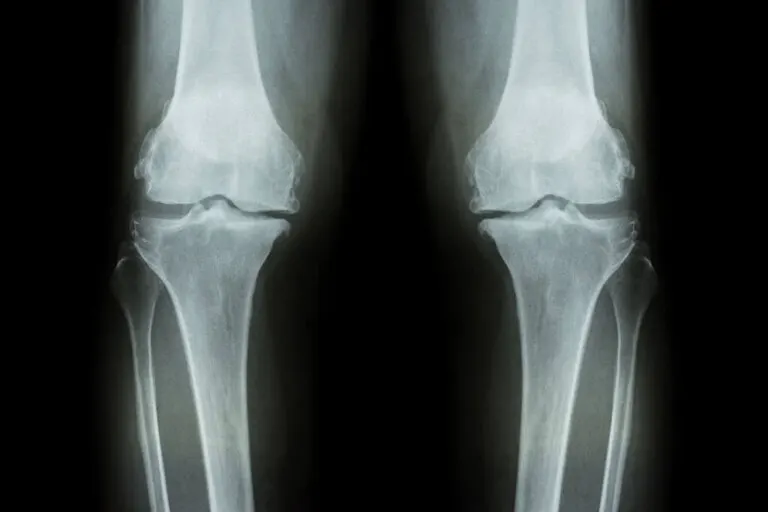

Pueden existir alteraciones dentro de las células del cartílago articular, una alteración de los llamados condrocitos y del hueso subcondral, que deriva en una temida falta de resistencia a la presión y la falta también de la elasticidad del cartílago, que se va deteriorando y adelgazando.

- En etapas más avanzadas va apareciendo una ligera deformación, como un cambio en la alineación de la rodilla, generalmente metiéndose hacia adentro las piernas.

¿Y por qué ocurre? Básicamente por que la rodilla se deforma por la reacción del hueso articular ante la artrosis, se forman entonces una especie de bordes en la articulación que reciben el nombre de osteofitos.